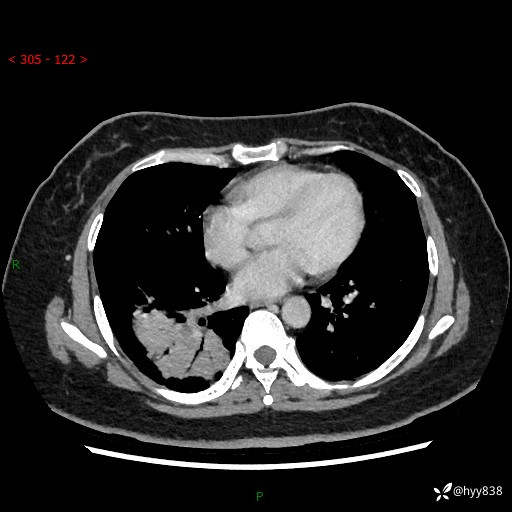

增强动脉期+静脉期